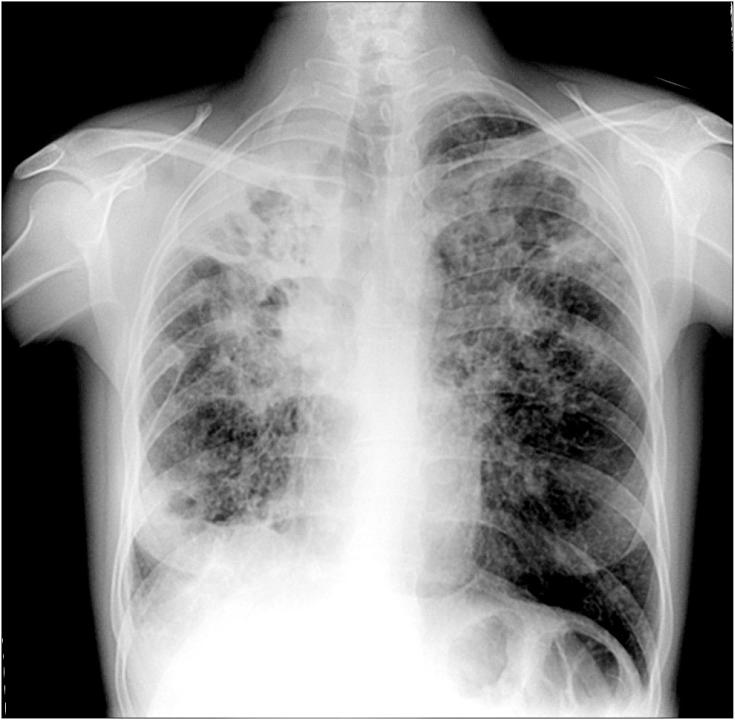

Рентгенография грудной клетки выявила инфильтраты над двусторонними верхними долями (рис. 1).Были подозрения на туберкулез легких (ТБ). Однако три набора экспресс-окрашивания мокроты кислотой были отрицательными. Для дальнейшей оценки поражений легких компьютерная томография грудной клетки (КТ) (рис. 2) неожиданно показала остеолитические поражения на теле девятого позвонка. Магнитно-резонансная томография (МРТ) позвоночника продемонстрировала повышенный сигнал в тех же позвонках с фокальной эрозией нижней замыкательной пластинки и образованием абсцесса над правым нижним углом тела позвонка, что указывает на спондилодисцит (рис. 3А и В).Было подозрение на компрессию нервных корешков. Были выполнены хирургические процедуры, включая ламинэктомию, дискэктомию и костную пластику. Боль постепенно прошла после операции. При гистологическом исследовании в образце обнаружены кислые бациллы, поэтому были назначены противотуберкулезные препараты. Позднее при посеве мокроты и спинномозговой ткани было получено микобактерий туберкулеза .

Рисунок 1.

Рентгенография органов грудной клетки, выявляющая инфильтраты над верхними долями с обеих сторон.